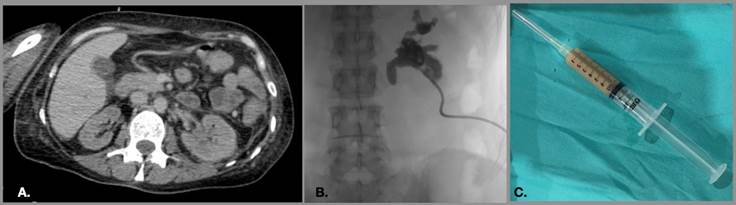

Con el fin de descomprimir la vía urinaria y obtener muestras para cultivo, los pacientes con sospecha de pionefrosis son sometidos a derivación urinaria mediante nefrostomía (Figura 8). Durante el acceso se debe cuidar administrar pequeñas cantidades de contraste, ya que al administrar mayor cantidad de líquido a la vía urinaria que ya se encuentra presurizada, se puede incrementar el riesgo de sepsis.9

Figura 8. (A) Corte axial de tomografía computada en fase venosa que muestra estriación de la grasa perirrenal izquierda e incremento en las dimensiones de este. Ante la sospecha de pionefrosis posterior a caracterización por ultrasonido, se decide realizar nefrostomía (B) que en la imagen de control muestra defectos de llenado en el sistema colector. (C) Se obtuvieron muestras de apariencia purulenta que fueron enviadas a cultivo para determinar el tratamiento.

Figura 8